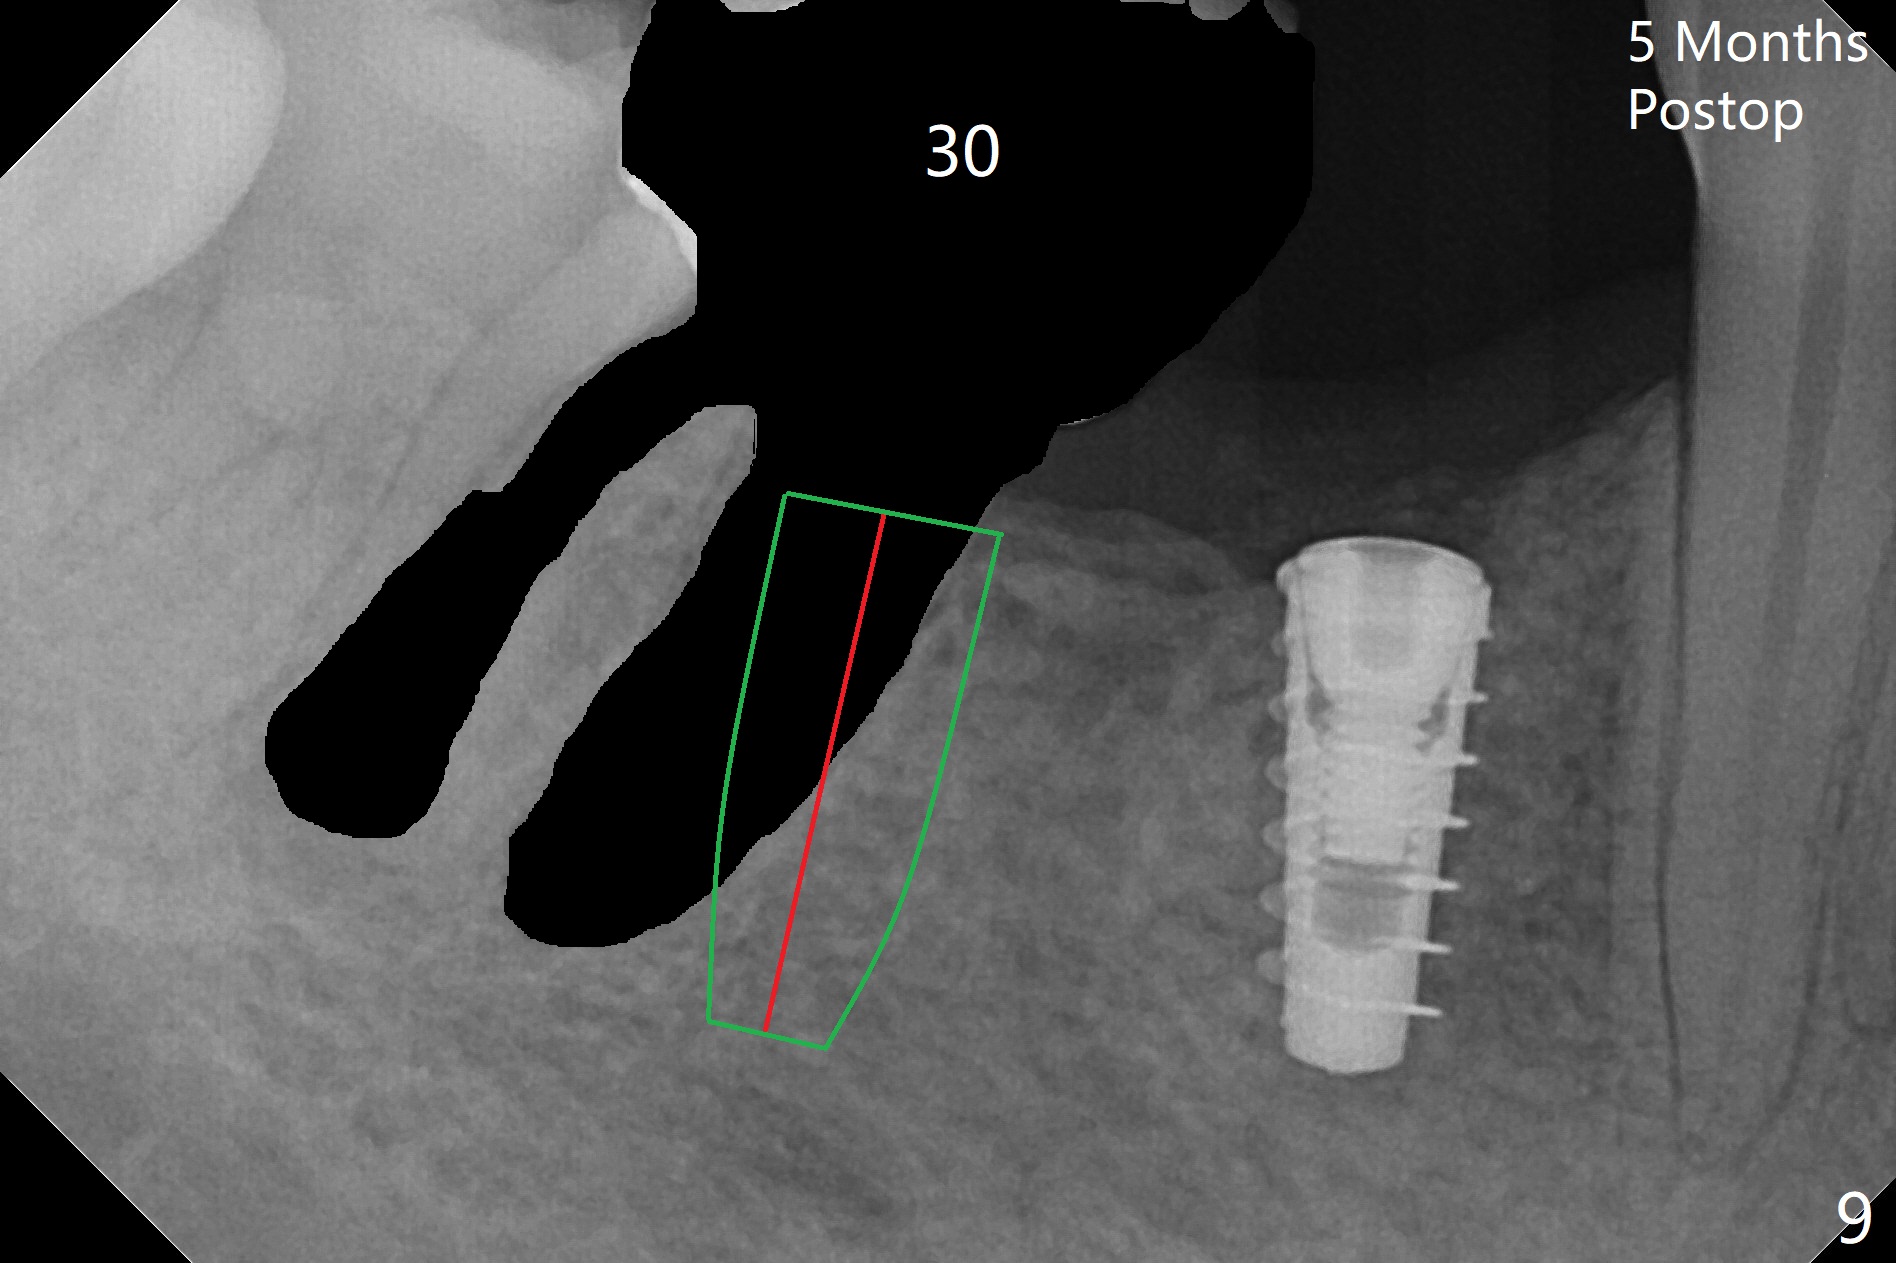

The patient returns for implant placement 11 months post extraction of #28 and 29. With flapless manner, initial osteotomy happens to drop into the original socket of #28 (Fig.4). After use of 3.3 mm Magic Drill (MD) and Final Drill for 15 mm, a 4x11 mm dummy implant is placed (Fig.5). It appears that the implant is long for the site (red dashed line: Mental Loop). However, a definitive implant (4x9 mm, IBS) has difficulty to reach its depth (Fig.6). After several rounds of untorque and retorque, the implant does not seat completely (Fig.7, implant driver disengagement) with autogenous bone placed distal (>). Retrospectively, a larger MD should have been used (3.8 mm) for complete seating in the dense bone. In fact she is post breast cancer treatment with 50% chance of relapse. The patient returns for follow up 1.5 months postop (Fig.8). The wound has healed. Impression is taken 5 months postop (Fig.9). When the crown is cemented, food impaction is an issue between the implant crown and crown at #30. Since the tooth #30 is mesially tilted with distal open margin and apical infection, the tooth will be extracted. Osteotomy is going to be initiated in the mesial slope of the mesial socket (Fig.9 red line). An implant will be placed more or less in the mesial socket (green box).